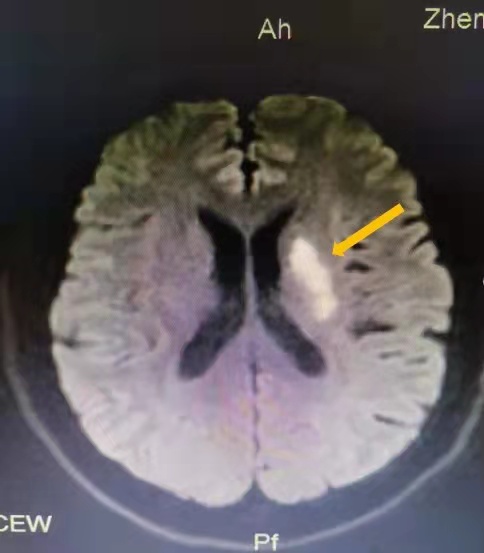

病例3 患者为男性,28岁,在单位午休时,突然出现左手麻木,持续约3分钟后症状缓解,发作4次,急忙来到郑州大学第二附属医院就诊。磁共振检查结果提示:右侧大脑中动脉重度狭窄,供血区域多发散在急性脑梗死病灶。在住院期间,医生为患者完善高分辨率磁共振脑动脉斑块分析、血管炎抗体等检查后,诊断患者为脑动脉血管炎。

庆幸的是,患者及时就诊,及时治疗,最后康复了。